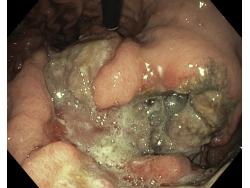

Nowotwory przewodu pokarmowego